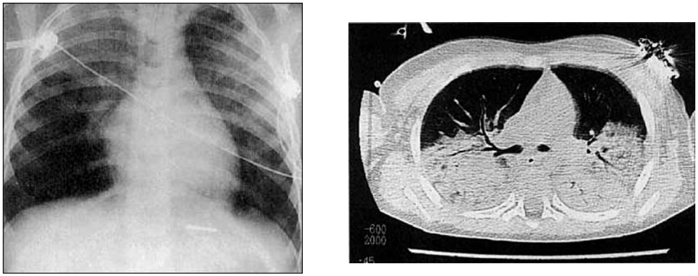

Paciente vítima de atropelamento, sexo masculino, 45 anos, altura 1,85 m, peso 80 Kg, após 3 dias na UTI, em IOT sob VM Modo Pressão Suporte com SatO2 = 88%, Pressão suporte (PS) = 25 cmH2O, FiO2 = 50%, Peep = 5 cmH2O, Volume corrente (VC) = 650 mL com hipoxemia de PaO2 = 57 mmHg, apresentou os seguintes exames de imagem, sendo descartada causa cardíaca.

(Arquivo pessoal; imagens usadas com autorização)

Qual a medida ventilatória inicial recomendada para esse paciente?